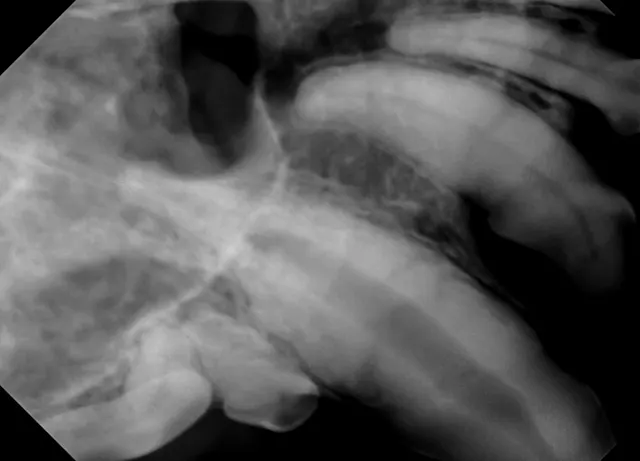

FIGURE 1A

Resorption of the right maxillary canine root in a 3-year-old English bulldog.

3. Root Canal Therapy

Root canal therapy, an advanced procedure with guarded prognosis, can be used to treat cases of internal and external tooth resorption.1 Because tooth resorption in dogs is idiopathic and possibly progressive, long-term success of root canal therapy may not affect the clinical course of tooth destruction.